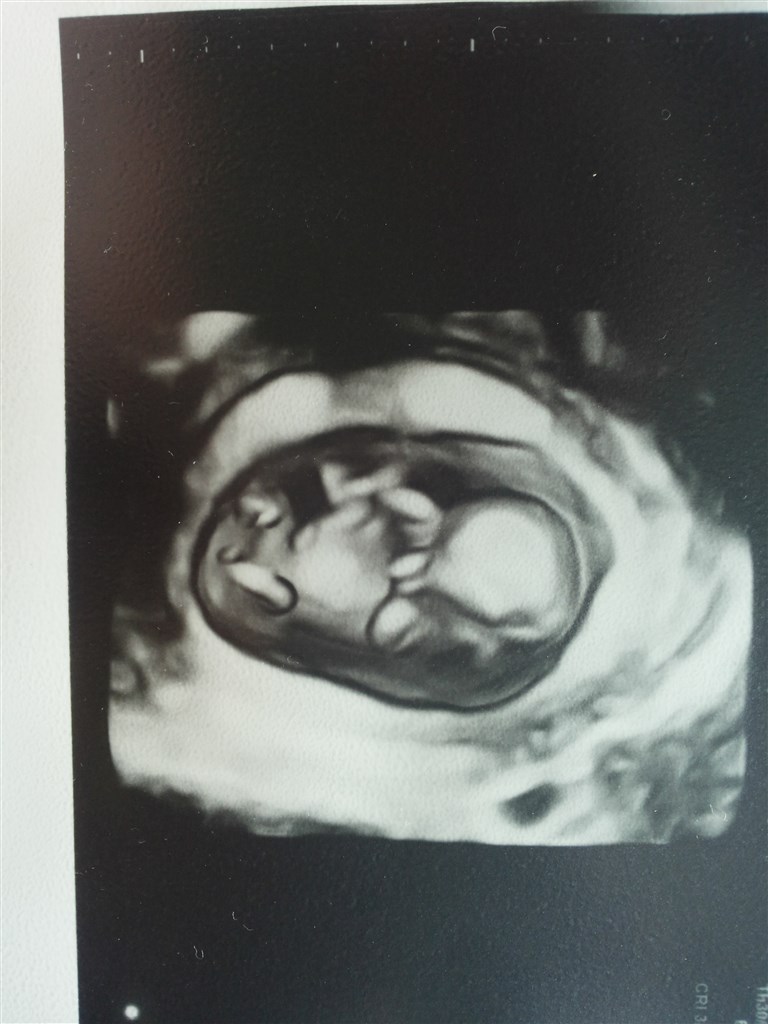

Jeg førstegangs fødende og græd som pisket da jeg første gang hørte vores lille fis ♥ Vi så 3D og fik en masse billeder med hjem som vi stolt viste frem

Vedhæftede fotos (klik for at se i fuld størrelse)